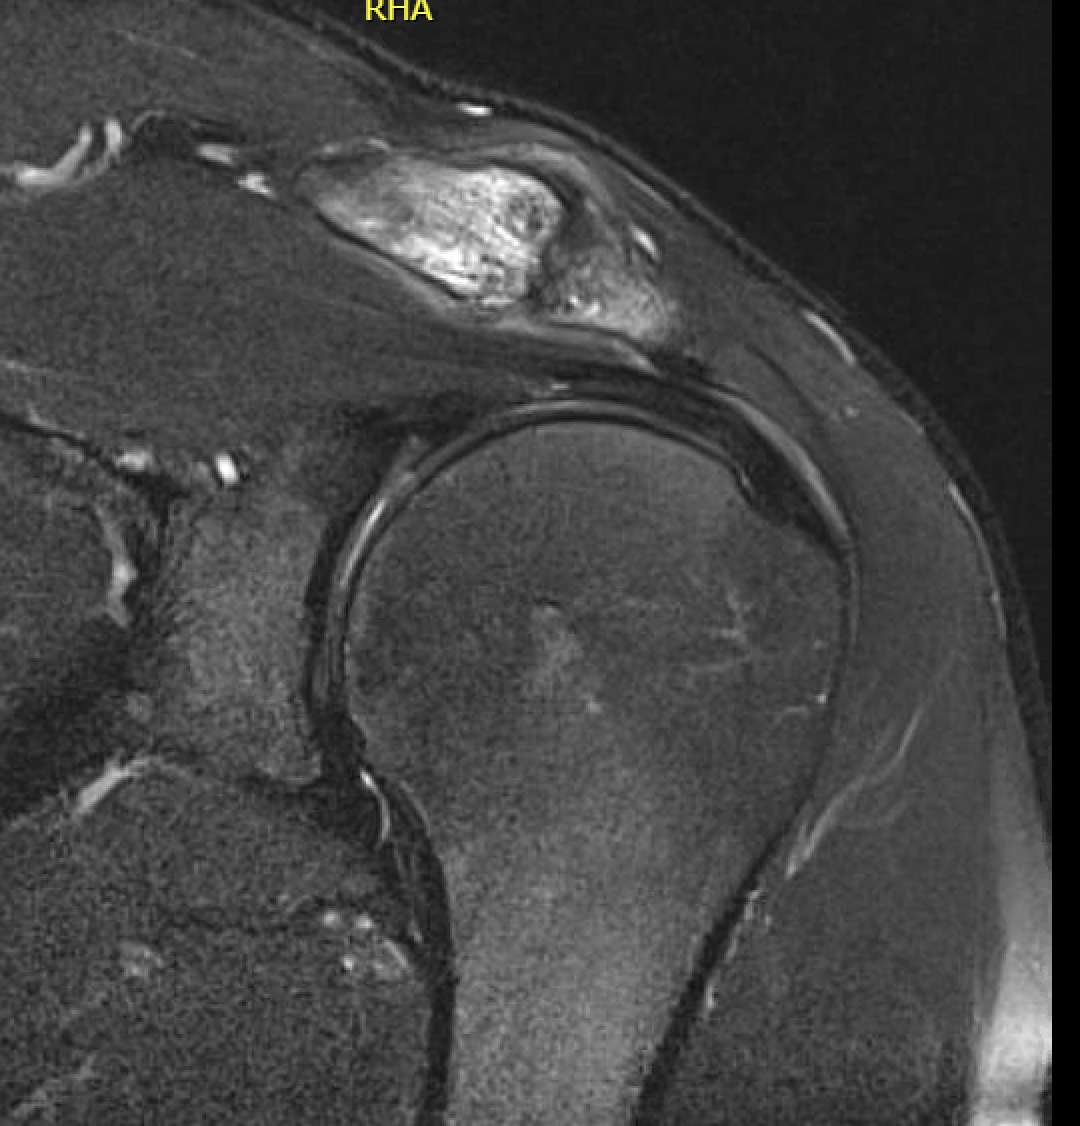

MRI

Acromioclavicular osteoarthritis

Grade I: Normal

Grade II: Capsular distension, bone marrow edema, mild joint narrowing

Grade III: Capsular distension, joint space narrowing, marginal osteophytes

Grade IV: Markedly abnormal ACJ with large osteophytes

Acromioclavicular joint osteolysis